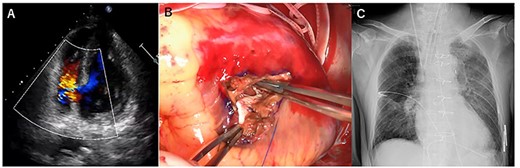

However, he again developed severe cardiogenic shock suddenly on POD 14 (Fig. 3A). Transthoracic echocardiography showed PMR and severe mitral regurgitation (Fig. 3B–D). VA-ECMO was restarted on the general ward, and the patient was transferred directly to the OR. Emergency mitral valve replacement with a biological prosthesis (Magna Ease 27 mm, Edwards Lifesciences, Irvine, CA, USA) was performed in the standard fashion. Intraoperatively, the ruptured posterior papillary muscle was confirmed. VA-ECMO could be weaned immediately after the surgery. After the two emergency operations, his course was uneventful, and he gradually recovered. He was then transferred to another hospital on POD 77 for rehabilitation.

X-ray at 14 days after first operation (A). transthoracic echocardiographic images showing posterior papillary muscle rupture (arrowhead, B) (C). Posterior papillary muscle rupture (arrowhead, D).